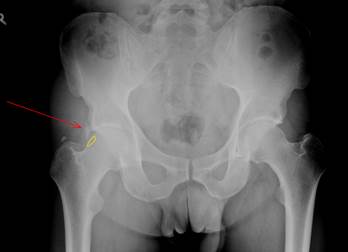

Beispiel eines FAI bei einem 42 jährigen Patienten der rechten Hüfte (links im Bild). Beckenübersichtsaufnahme.

Gleiches Beispiel eines FAI bei einem 42 jährigen Patienten der rechten Hüfte (links im Bild). Der rote Pfeil markiert eine Verknöcherung des Labrums, der gelbe Kreis den „Bump"